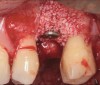

Fig 9. Treatment of peri-implant mucositis: plaque accumulation and mucosal inflammation.

Figure 9

Fig 10. Traumatic impingement of the pontic on the peri-implant mucosa.

Figure 10

An important aspect of both professionally and patient-administered plaque removal is the cleanliness of the implant-supported restoration. A cohort study on 23 patients demonstrated that 74% of implants had no accessibility to proper oral hygiene and 48% of implants presenting with peri-implantitis were those that were not cleansable.17 The non-fitting or non-cleansable overhanging prostheses, therefore, should be considered iatrogenic factors that contribute to the development of peri-implantitis. Similarly, incorrectly positioned implants or foreign bodies such as impression material or excess luting cement can contribute to increased biofilm accumulation and hence favor the development of peri-implant diseases.10 Correction or elimination of these factors (eg, prosthesis removal and adjustment/replacement, if necessary) should be a principal component of the treatment of peri-implant mucositis (Figure 9 through Figure 11).